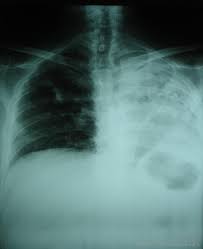

Visceral pleura and parietal pleura that encloses pleural space filled with pleural fluid. 18 can pleural effusions recur? Both costophrenic angles are obliterated indicating bilateral pleural effusion. Pleural infection pleural inflammation pleural malignancy (most often occurring with the lung or breast) in exudative effusion, the ratio of protein in pleural fluid to protein in serum is 0.5 or higher, the lactate dehydrogenase (ld) level is 200 iu or higher, and the. Pleural effusions are very common, and physicians of all specialties encounter them.

The level of the effusion is higher on the right side. Visceral pleura and parietal pleura that encloses pleural space filled with pleural fluid. In healthy lungs, these membranes ensure that a. Fluid gathers in the lowest part of. When blunting of these costophrenic angles is seen, it is suggestive of. Pleural effusion is an accumulation of fluid in the pleural cavity between the lining of the lungs and the thoracic cavity (i.e., the visceral and parietal pleurae). Mri showing bilateral pleural effusion (source). Bilateral pleural effusions and bilateral lower lung atelectasis.

The level of the effusion is higher on the right side. When blunting of these costophrenic angles is seen, it is suggestive of. Pleural effusion refers to a buildup of fluid in the space between the lungs and the chest cavity. Fluid gathers in the lowest part of. There is enlargement of the cardiac outline, partly obscured by the pleural effusion. Mri showing bilateral pleural effusion (source). Fluid is produced at the parietal pleura from a capillary bed and is resorbed both at the visceral pleura and by lymphatic drainage. Ct scans show more detail than. In healthy lungs, these membranes ensure that a. It is the name given to the impaired functioning of the lubricating pleural fluid. In the usa approximately 1.5 million people are diagnosed with a pleural effusion each year 2. Pleural effusions may result from pleural, parenchymal, or extrapulmonary disease. Pleural infection pleural inflammation pleural malignancy (most often occurring with the lung or breast) in exudative effusion, the ratio of protein in pleural fluid to protein in serum is 0.5 or higher, the lactate dehydrogenase (ld) level is 200 iu or higher, and the.

Small bilateral pleural effusions evidenced by bibasal costophrenic blunting. Intravascular oncotic pressure decreases, which leads to the pleural effusions. Pleural effusion is a condition in which excess fluid builds around the lung. On examination, she had bilateral pedal oedema, tender mild hepatomegaly, bilateral pleural effusion and ascites. The first subchapter focuses on the pleural effusion 8 minutes video about what a doctor should know about pleural effusion diagnosis by chest x ray some data was taken from.

Some key features to keep in mind for the appearance of pleural. Both costophrenic angles are obliterated indicating bilateral pleural effusion. There is enlargement of the cardiac outline, partly obscured by the pleural effusion. Bilateral pleural effusions and bilateral lower lung atelectasis. Bilateral interstitial lung disease is again seen present on the previous study primarily in. Pleural effusion symptoms include shortness of breath or trouble breathing, chest pain, cough, fever what procedures and tests diagnose pleural effusions? Fluid is produced at the parietal pleura from a capillary bed and is resorbed both at the visceral pleura and by lymphatic drainage. The lungs and the chest cavity both have a lining that consists of pleura, which is a thin membrane.

Pleural space contains about 0.3 ml/kg body weight of pleural fluid. In the usa approximately 1.5 million people are diagnosed with a pleural effusion each year 2. Pleural effusions are very common, and physicians of all specialties encounter them. Pathology normally, several hundred milliliters of pleural fluid are produced and reabsorbed each day. Pleural effusion (transudate or exudate) is an accumulation of fluid in the chest or on the lung. In healthy lungs, these membranes ensure that a. Fluid gathers in the lowest part of. Learn step 2 and shelf essentials in a free 10 min video. Mri showing bilateral pleural effusion (source). Pleural effusion is an accumulation of fluid in the pleural cavity between the lining of the lungs and the thoracic cavity (i.e., the visceral and parietal pleurae). Some key features to keep in mind for the appearance of pleural. Both costophrenic angles are obliterated indicating bilateral pleural effusion. Visceral pleura and parietal pleura that encloses pleural space filled with pleural fluid.